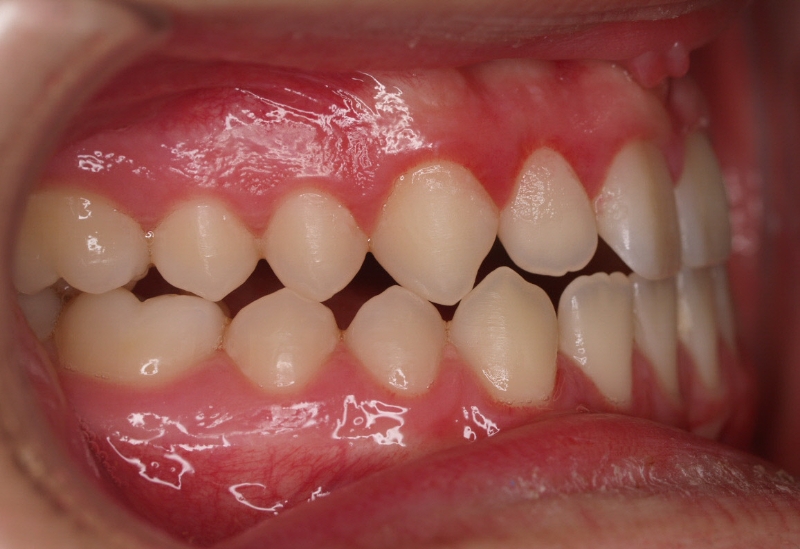

El paciente E.A. acude a nuestra consulta por diastema inferior y ausencia de contactos en los sectores laterales.

1) Arreglamos el problema funcional (lengua baja). Colaboramos con la logopeda Ana Muñoz.

2) Colocamos aparatología fija (brackets Damon) arriba y abajo.